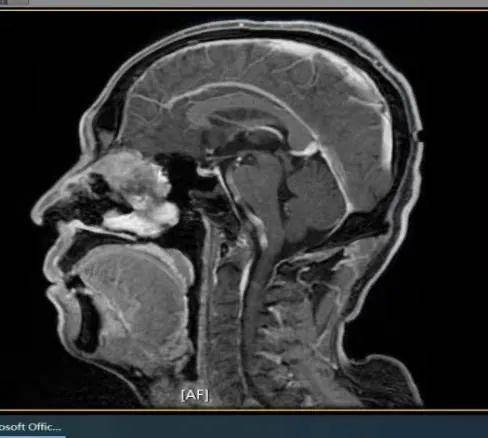

患者男,59岁,因左鼻腔涕中带血40余天入院,入院CT、MRI示前颅底肿瘤,侵犯前颅底骨质及硬脑膜。入院诊断:前颅底肿瘤。入院后在病房行活检示(左侧鼻腔)嗅神经母细胞瘤,排除手术禁忌症后行全麻下经鼻内镜下前颅底肿瘤及前颅底部分骨质磨除、硬脑膜切除,鼻颅底重建手术。

CT、MRI示前颅底肿瘤,侵犯前颅底骨质及硬脑膜